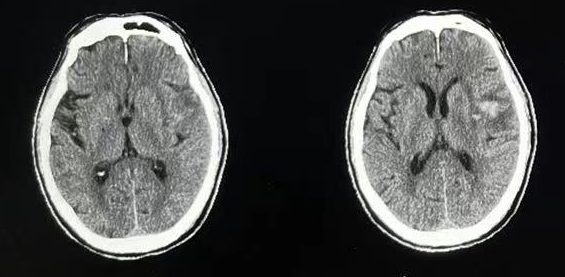

▲术后CT

随后给予脱水降颅压、预防感染、营养神经、补液等对症治疗,2天后拔除血肿腔引流管。复查CT显示脑内血肿清除满意。